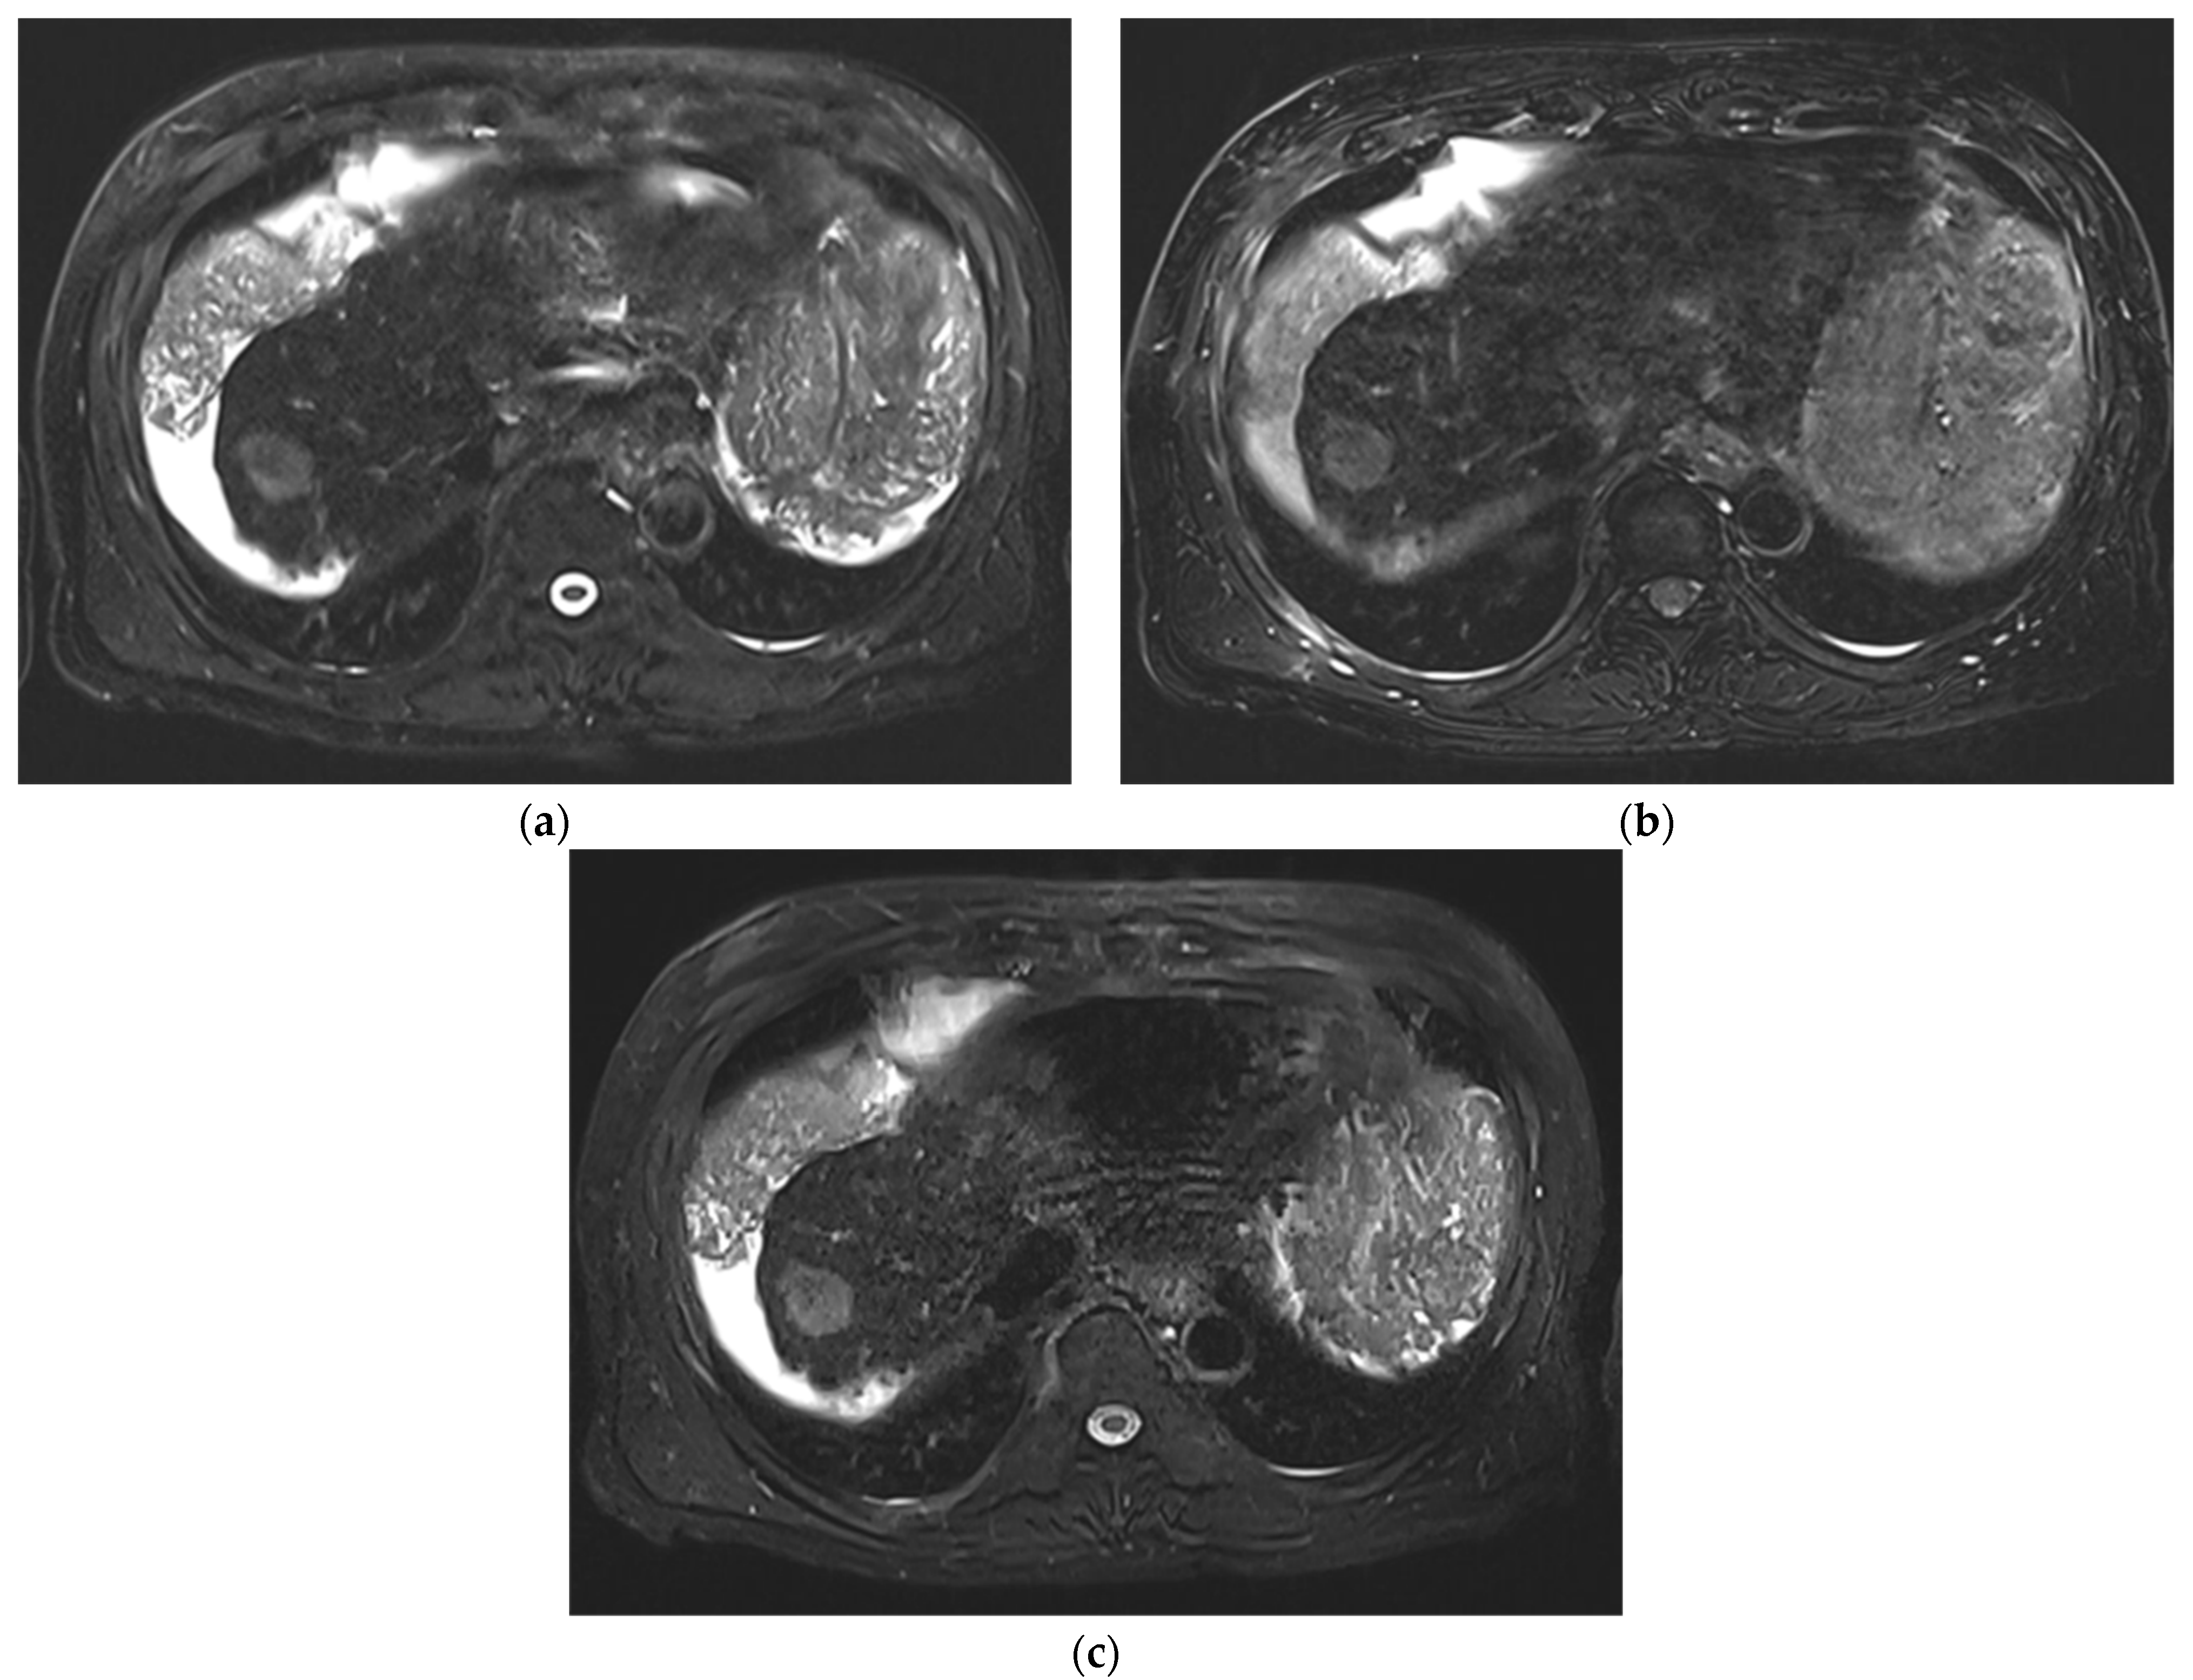

Improved Single Breath-Hold SSFSE Sequence for Liver MRI Based on Compressed Sensing: Evaluation of Image Quality Compared with Conventional T2-Weighted Sequences

3. Results

3.1. Subjective Image Quality

3.2. Lesion Assessment

4. Discussion